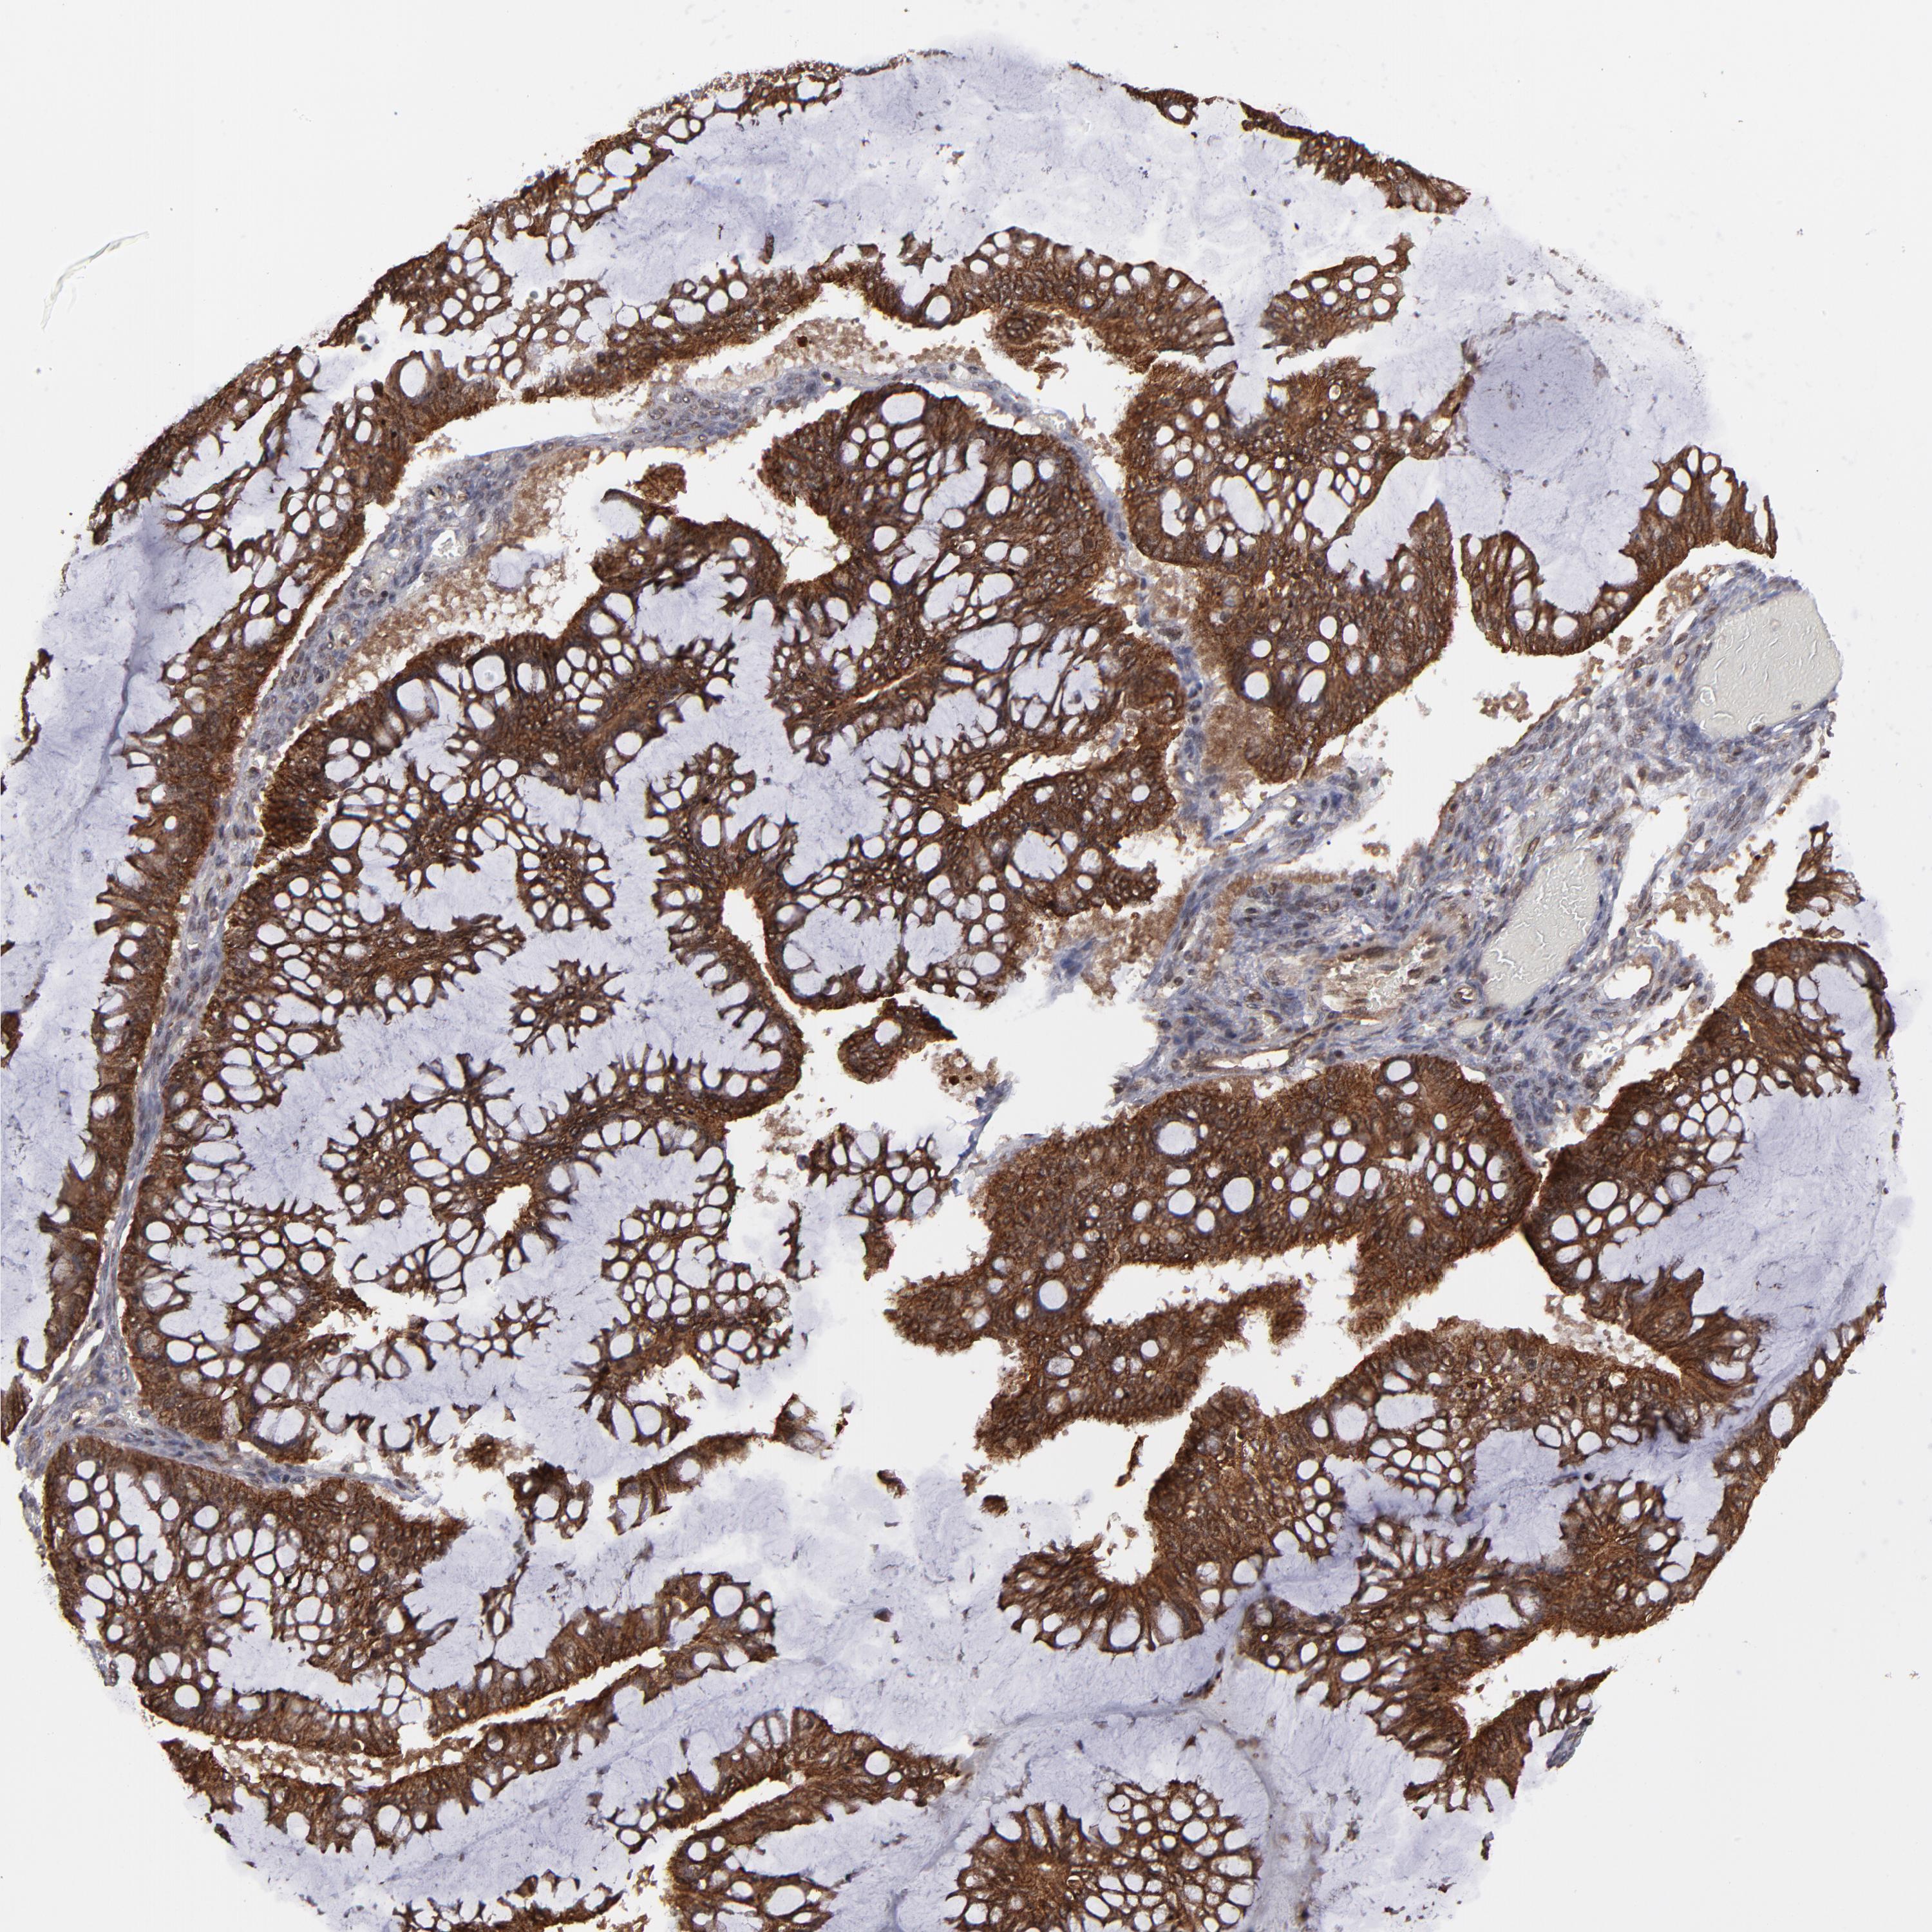

OVARIAN CANCER - Protein expressioni

A mouse-over function shows sample information and annotation data. Click on an image to view it in a full screen mode. Samples can be filtered based on level of antibody staining by selecting one or several of the following categories: high, medium, low and not detected. The assay and annotation is described here.

Note that samples used for immunohistochemistry by the Human Protein Atlas do not correspond to samples in the TCGA dataset.

Antibody stainingi

Antibody staining in the annotated cell types in the current human tissue is reported as not detected, low, medium, or high, based on conventional immunohistochemistry profiling in selected tissues. This score is based on the combination of the staining intensity and fraction of stained cells.

Each image is clickable and will lead to virtual microscopy that enables deeper exploration of all samples and also displays staining intensity scores, fraction scores and subcellular localization as well as patient and tissue information for each sample.

Antibody HPA003067

Staining

High

Medium

Low

Not detected

Intensity

Strong

Moderate

Weak

Negative

Quantity

>75%

75%-25%

<25%

None

Location

Nuclear

Cytoplasmic/membranous

Cytoplasmic/membranous,nuclear

Cystadenocarcinoma, serous, NOS

Cystadenocarcinoma, mucinous, NOS

Carcinoma, endometroid